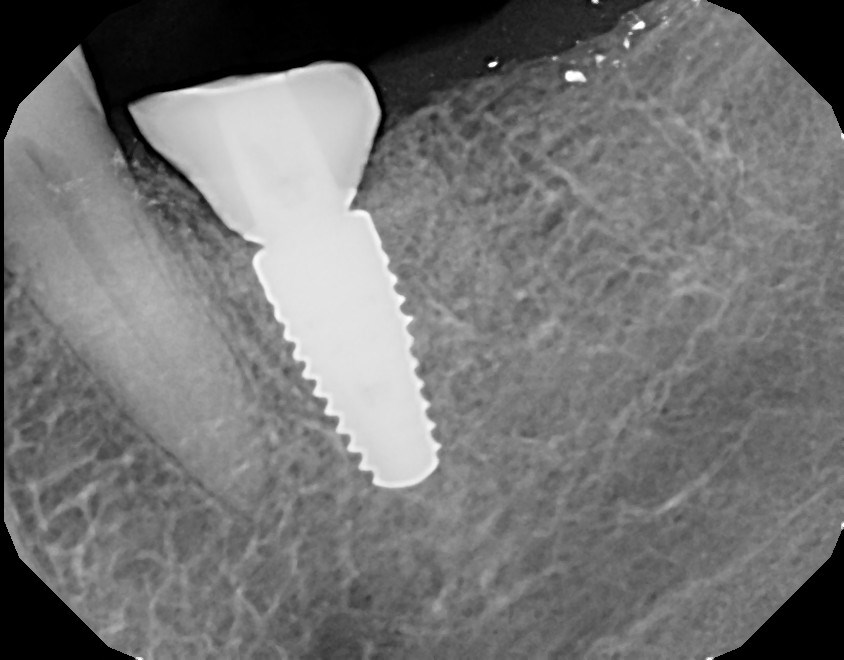

Fig 18. Radiograph of the final restoration after the customized emergence profile had been developed, replicating a natural emergence.

Figure 18

After a 6- to 8-week healing period, the custom healing abutment was removed to allow for a digital scan of the area as an alternative to conventional impression-taking (Figure 15 and Figure 16). An intraoral scan body was used to capture the soft-tissue profile and implant positioning with an intraoral scanner (CEREC® Omnicam, Dentsply Sirona) (Figure 17). Final seating of the restoration was performed with radiographic confirmation (Figure 18). The implant crown demonstrated a natural emergence profile to replace the mandibular first molar with optimized tissue fill in the interproximal regions (Figure 19).